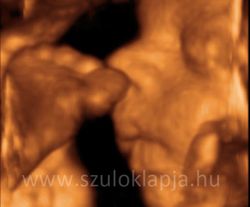

A baba érzi a magzatvízbe átjutott ízeket

A tények és vizsgálati adatok alátámasztják, hogy ízérzékelés létezik már magzati korban is.

A kismama által fogyasztott ételek, italok összetevői részben bejutnak a magzatvízbe. Tesztek azt mutatják, hogy a baba magzatvíz-kortyolásainak száma növekszik édes anyagok hatására, és csökken savanyú, vagy keserű anyagok esetében.

UH fotók: Beleznay Katalin